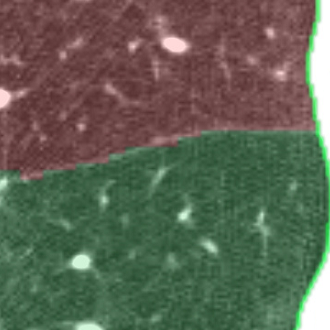

We applied the described segmentation pipeline to the 14 testing datasets which were not used for training and validation. Segmentation including postprocessing takes less than 6 seconds for a case. We compared our method to two other approaches: 1. a non-deep-learning-based automatic method [Lassen et al.(2013)Lassen, van Rikxoort, Schmidt, Kerkstra, van Ginneken, and Kuhnigk] 2. the same u-net as proposed but without weighting. The mean distance from the visible fissure improved to 1.46 mm (without weighting: 2.08 mm). See Figure 2 for plots and Figure 3 for screenshots.

We trained a 3D u-net for a lung lobe segmentation task and showed that emphasizing the lobar boundaries in the loss function improved the segmentation results (see Figure 2 and 3). The segmentation quality is comparable to the method proposed in [Lassen et al.(2013)Lassen, van Rikxoort, Schmidt, Kerkstra, van Ginneken, and Kuhnigk] and even slightly better for the left lobes. This study was performed on a small amount of data. In future work, we plan to train with the same architecture on a much larger database including a wide range of pathologies and performing an extensive evaluation with participation in the LOLA11 [LOLA11()] challenge.